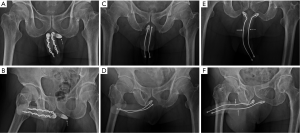

As a rule a circumferential approach was standard for semirigid, mechanical prothesis such as AMS600, AMS650, AMS Dynaflex, Duraphase (Figure 2A), Mentor malleable, Mentor acuform; a penoscrotal incision was used for implanting AMS ambicor and an extend pubic approach (Figure 2B,C) was specifically used for performing AMS700 CX implantation.

The model of prosthesis was recorded. Follow-up of patients including prosthesis survival, revision or end of patients’ life till August 2013. An anterior-posterior view of pelvis was undergone whenever patient revisited for either re-check or close observation. Proximal migration occurred merely in patients with semirigid prosthesis implant in 2 and 15 men to conventional and advanced group respectively (P=0.04) (Figure 4). Furthermore the prosthesis loss and revision surgery were analyzed and made when required (Figure 5). Six males concerning the penile length underwent penile elongation uneventfully (Figure 2A). Statistically student’s t-test or chi-squared test was either applied whenever necessary.